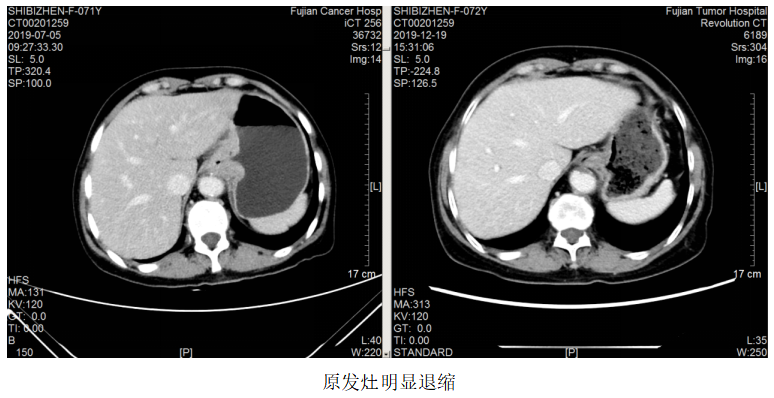

图1.2019.7.5影像(基线评估)

诊断:食管胃交界腺癌腹腔、腹膜后、左腋窝、左锁骨区淋巴结转移脑转移(cT4aN3M1,IV期,HER2扩增,MSS,PD-L1-)

一线治疗:2019.7.12~10.24予FOLFOX方案(奥沙利铂110mg+左亚叶酸钙300mg+5-Fu 2.75)化疗8周期,曲妥珠单抗220mg靶向治疗7次。

局部放疗:2019.7.23~2019.8.7予脑转移灶调强放疗DT3900CGy/13F。

疗效评估:PR。